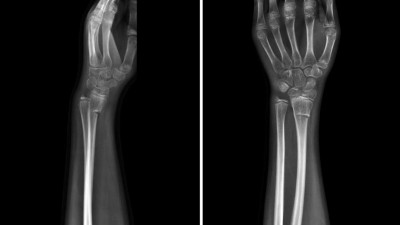

Praktische Tipps zur Radiusosteosynthese: Dorsale Schraubenüberstände vermeiden

Die palmare Plattenosteosynthese am distalen Radius hat sich etabliert, birgt jedoch bedeutende Risiken wie Schraubenüberstände, die zu Strecksehnenrupturen führen können. Moderne Bildgebung hilft, die Gefahr frühzeitig zu erkennen.

Berliner Dom/© Photocreo Bednarek / Stock.adobe.com, Ärzteteam führt Hüftoperation durch/© ATRPhoto / stock.adobe.com (Symbolbild mit Fotomodell), Ein älteres Pärchen fährt Fahrrad/© Halfpoint / stock.adobe.com (Symbolbild mit Fotomodellen), Frau greift an ihre Ferse/© Satjawat / stock.adobe.com (Symbolbild mit Fotomodell), Distale Radiusfraktur/© Joel bubble ben / stock.adobe.com, Frau bei Knochenmineraldichte-Messung/© gelmold / stock.adobe.com (Symbolbild mit Fotomodell), Viele Ärzte versorgen einen Patienten/© Monkey Business / Stock.adobe.com (Symbolbild mit Fotomodellen), Röntgenbild Hüftprothese/© oceandigital / Fotolia, Transmurale Ruptur der Supraspinatussehne/© Wahal N et al. / all rights reserved Springer Medizin Verlag GmbH, Bluttransfusion im Rettungshubschrauber/© [M] Chalabala / Stock.adobe.com, Physiotherapeutin behandelt Fußbeschwerden/© aldomurillo / Getty Images / iStock (Symbolbild mit Fotomodellen), Narbe nach Kniegelenkersatz-Operation/© GalinaSt / stock.adobe.com (Symbolbild mit Fotomodell), DGOU Logo/© Deutsche Gesellschaft für Orthopädie und Unfallchirurgie, Berlin/© eyetronic / Stock.adobe.com, Hallux valgus/© Springer Medizin, Modell des Kniegelenks/© edwardolive / Stock.adobe.com (Symbolbild), Lumbale Spinalkanalstenose/© Birkenmaier C & Fuetsch M / all rights reserved Springer Medizin Verlag GmbH, Anteriore Schulterluxation im Röntgenbild/© Spagna G et al. / all rights reserved Springer Medizin Verlag GmbH, Chirurginnen und Chirurgen im OP/© Tobilander / stock.adobe.com (Symbolbild mit Fotomodellen), Schulterarthroskopie/© Issara / stock.adobe.com (Symbolbild mit Fotomodellen), Elektronenmikroskopisches Bild eines Biofilms an einer Titanoberfläche (Vergr. 1500:1)/© Holinka J, Windhager R doi.org/10.1007/s00132-016-3247-8 unter CC-BY 4.0, Primäre Hüftgelenkendoprothetik nach Azetabulumfraktur/© Hofmann GO et al. / Springer Medizin Verlag 2008, Osteosynthese einer distalen Radiusfraktur /© Mathias Ernert, Ärztin erklärt einem Patienten das Hüftgelenk/© Daisy Daisy / Stock.adobe.com (Symbolbild mit Fotomodell), Periprothetische Femurfraktur/© Springer Medizin, Vorderes Kreuzband/© Springer Verlag GmbH, MRT-Sequenz vom Knie/© Springer Medizin, Schweres Thoraxtrauma/© Christoph Nau · Birte Weber · Ingo Marzi / all rights reserved Springer Medizin Verlag GmbH, Ruptur der Rotatorenmanschette/© Springer Medizin, Wirbelkörper/© CreVis2 / Getty Images / iStock, Hallux valgus/© masanyanka / stock.adobe.com, Rotatorenmanschette/© Springer Verlag GmbH, Röntgenbild eines künstlichen Hüftgelenks/© Nicolas Larento / Fotolia, Minimalinvasive AC-Gelenk-Operation/© Springer Medizin, Rettungsassistenten liefern Notfallpatientin auf einer Trage in ein Krankenhaus ein/© Stephan Jansen / dpa / picture alliance, Idiopathische Skoliose/© Springer Medizin Verlag GmbH, Bandscheibenvorfall der LWS schematisch /© psdesign1 / Fotolia, Frau fasst sich an die Wade/© KSR / Fotolia , Liposarkom/© Davorin Wagner / Chirurgie im Bild, Narbe nach Kniegelenkersatz/© Miriam Dörr / Fotolia (Symbolbild mit Fotomodell), Weiße Tabletten im Blister/© bogo-service / Fotolia